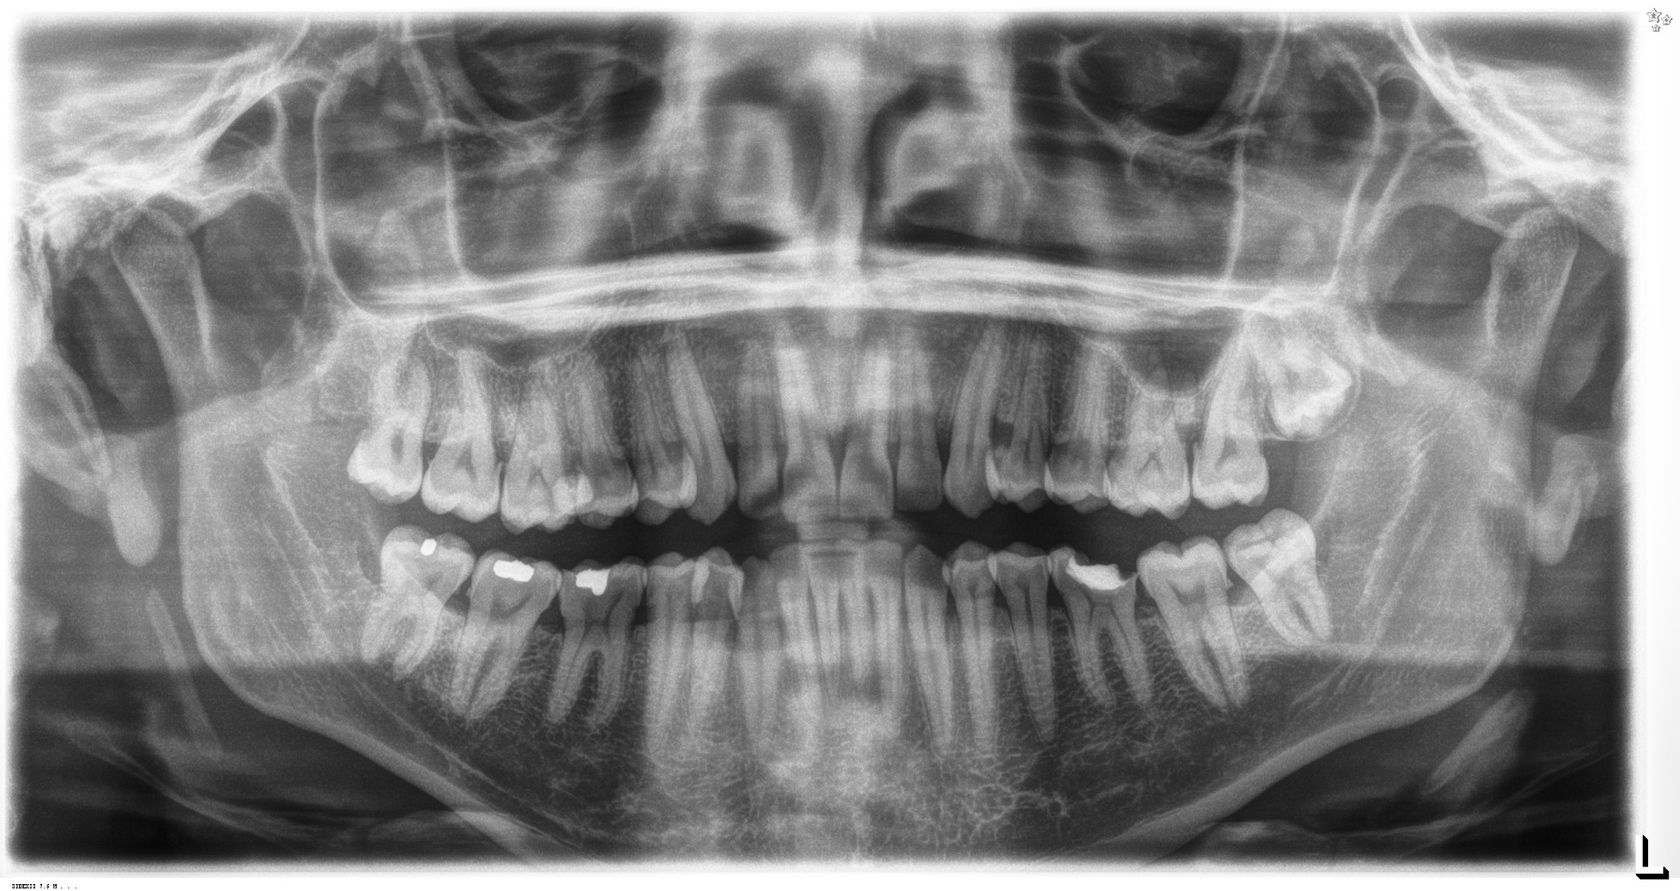

El medico dijo que no podía atacar la pieza, sin antes tener una placa para evaluar en estado de los dientes.

me mando a casa con una orden de rayos x (Panorámica)

le entregué la placa y ella me dijo que tenia que hacerme un tratamiento de conducto. pero debía ser la próxima semana, con un especialista.